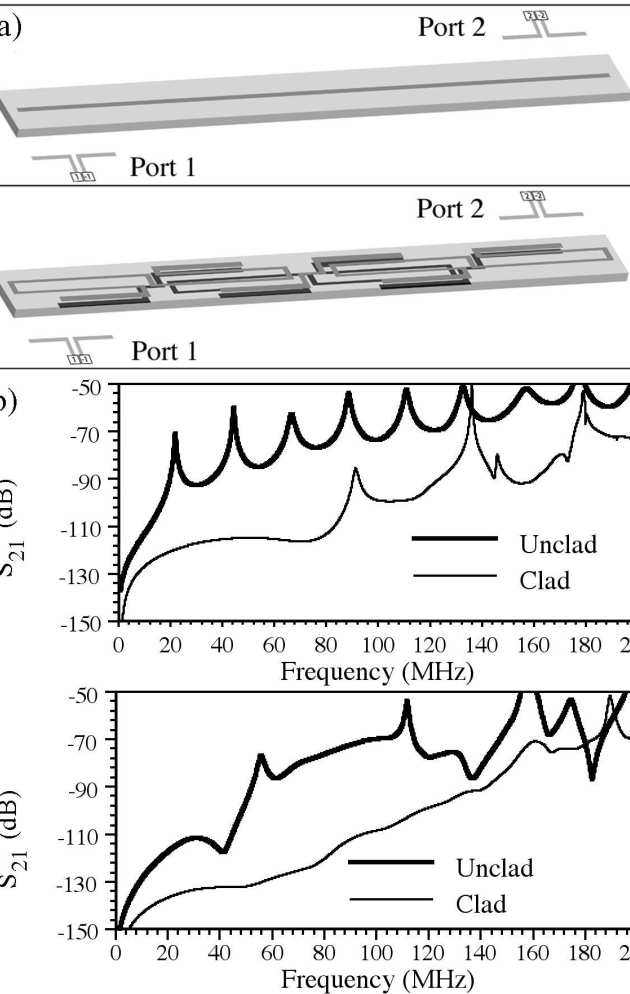

We have modeled a catheter-based RF receiver for internal magnetic resonance imaging. The device consists of a double-sided thin-film circuit, mounted on a hollow catheter. The system was originally designed for biliary ductal imaging, but is also potentially useful for vascular imaging. Signals are detected using a resonant L-C circuit at the catheter tip, transmitted along the catheter using an array of coupled L-C resonators, and coupled into a conventional RF system using a demountable inductive transducer. Protection against external B1 and E fields is obtained by using figure-of-eight-shaped elements with an electrical length shorter than that of an immersed half-wave dipole. Electromagnetic modeling software (AWR Microwave Office) has been used to analyze a system designed for 1H imaging at 1.5 T, determine the effect of the tissue surround, demonstrate signal detection and transmission and verify intrinsic safety.

|---|

| Thin-film detector: a) and b) circuit, and c) integration on catheter. |

|---|

| Detector simulation: a) AWR model; b) frequency variations of S11 and S21 as predicted by AWR and MATLAB. |

|---|

| Simulation of electric decoupling: a) AWR models and b) frequency variations of S21 for wire and cable, with and without cladding. |